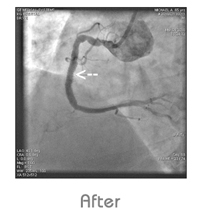

Angiogram

“FIRST TIME” Pukra (Kovai Heart Foundation) introduced World Class Out Patient Angiogram and Angioplasty (STENT).

• “Gold Standard” procedure for coronary artery occlusion, deduction and measurement.

“Walk in Walk out” within 30 Minutes after Angiogram now at KHF (KOVAI HEART FOUNDATION) - Angiogram Centre.